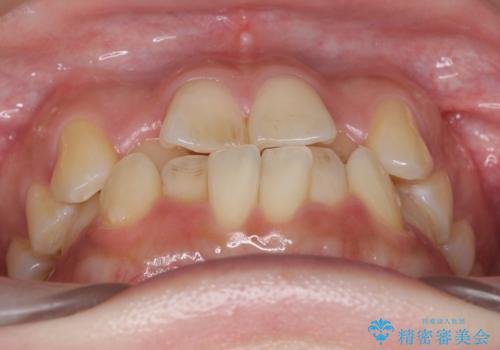

- 前歯のがたつき、受け口を主訴に来院。

上の前歯が二本裏側に入っていました。(反対咬合といいます)

上はワイヤー部分矯正、下はインビザライン(マウスピース)で部分矯正を行いました。

下の前歯を内側に入れる為、一本抜歯しています。

上の前歯のデコボコは激しく、かぶせ物で治療するとなると2本抜歯してブリッジになってしまいます。ダミーの歯の大きさも小さくなるため不自然になり下の歯のがたつきもあるためお勧めできません。

全体矯正で治そうとすると非抜歯ですとだいぶ口元が前に突出するのに加え、下の前歯が入りきらない可能性がありました。上下左右4本抜歯となるため、それを回避するのに下の前歯を1本抜歯して、下の前歯を確実に内側に入れています。